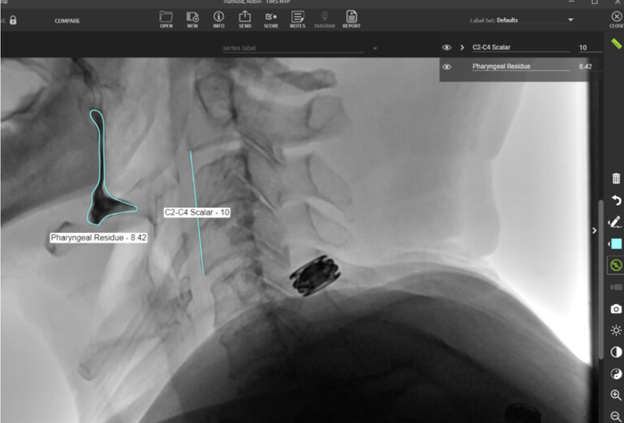

Total Pharyngeal Residue

Quick Takeaways

If there is pharyngeal residue after the swallow of the initial bolus, measure the amount. This data point can be used as described by the ASPEKT-C

Method.

Steps for Completion

Use the line tool to set the C2-C4 scalar.

Using the measurement tool, override the value and set it to 10 pixels. This allows us to create a 10x10 box representative of the C2-C4 squared space. Any subsequent measurements will then be scaled to the C2-C4 scalar (a percentage of 100).

Measure the pharyngeal residue with the freehand tool. TIMS will automatically determine the percentage of residue because of the work you completed with the scalar. The amount you obtain can be compared to the normative data.

In the example below, the pharyngeal residue is 8.42% of the C2-C4 squared space.

Note: By normalizing residue measurements to an individual’s anatomy using the C2-C4 scalar, clinicians can make more meaningful comparisons both within a study and across examinations.

Example: Use of the line and freehand tools to assess TPR in TIMS MVP.